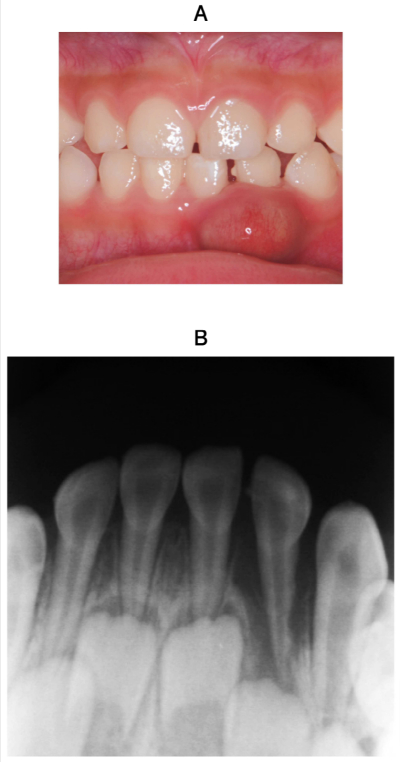

2歳10か月の男児。下顎乳前歯部の歯肉の異常を主訴として来院した。2か月前に転倒して下顎左側乳側切歯が挺出したため、近医で整復固定処置を受けたという。腫脹部に波動を触れる。自発痛はないが咬合痛がある。初診時の口腔内写真とエックス線写真を別に示す。

消炎後に行う処置はどれか。1つ選べ。

d. 感染根管治療